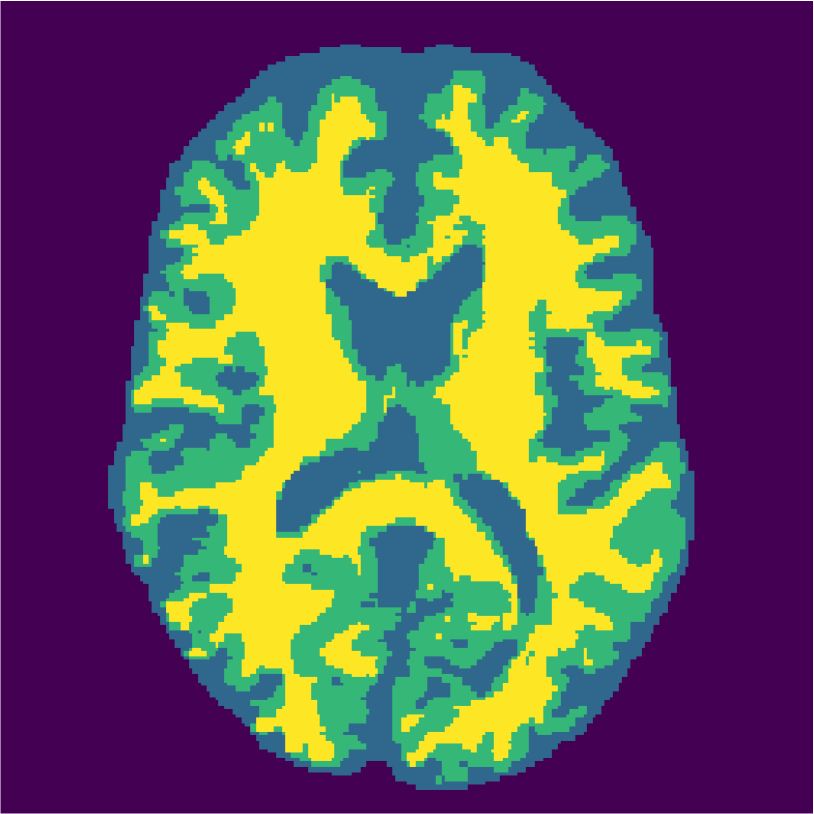

Appendix A describes the nuclear magnetic resonance (NMR) relaxation times for the tissues in the Brainweb anatomical models, for 1.5 and 3.0 Tesla field strengths. The tissues in the anatomical models are grouped into ”background” (BKG), ”cerebrospinal fluid” (CSF), ”gray matter” (GM), and ”white matter” (WM) to compose the ground truth segmentation labels for the simulated scans. The simulations result in images of 256 by 256 pixels, with a 1.0x1.0mm resolution. Figures 5(a) and 5(b) show examples of the Brainweb1.5T and Brainweb3.0T scan of the same subject. For all scans, we used a brain mask to strip the skull.

Figure 6 displays the manually selected patches and their position within the image. For both the source and target classifier, one target patch per tissue is insufficient to achieve good tissue classification performance (2 (top row): 0.631 and 0.613). However, the mrai-net classifier shows considerably better performance (0.223), using only one target patch per tissue. The proxy -distance also drops from near perfect separability (1.88) to near invariance (0.26). Randomly selecting (10 repeats) 1 target patch per tissue (Table 2 (bottom row)), shows worse performance of the mrai-net classifier, for both the classification error (0.250) as well as the -distance (0.41). Suggesting that purposive (information rich) sampling beats random sampling in this case.

Examples of the segmentation results on one of the target test images are shown in Figure 8 for experiment 2.1, Figure 9 for experiment 2.2, and Figure 10 for experiment 2.3. Examples are shown after using 1 target patch per tissue for training, and after using 100 target patches per tissue for training. The results show that only the mrai-net classifier is able to predict a segmentation that approaches the ground truth with only 1 target patch per tissue for training (error for experiment 2.1 = 0.269, experiment 2.2 = 0.403, experiment 2.3 = 0.320), while the source and target classifiers cannot (source error for experiment 2.1 = 0.667, experiment 2.2 = 0.653, experiment 2.3 = 0.435; target error for experiment 2.1: 0.591, experiment 2.2: 0.614, experiment 2.3 = 0.596). After using 100 patches the source and target classifiers can predict a gross segmentation of WM, GM and CSF (source error for experiment 2.1 = 0.213, experiment 2.2 = 0.384, experiment 2.3 = 0.363; target error for experiment 2.1: 0.205, experiment 2.2: 0.368, experiment 2.3 = 0.368), but the mrai-net classifier prediction shows more details and a lower tissue classification error (error for experiment 2.1 = 0.111, experiment 2.2 = 0.276, experiment 2.3 = 0.284).